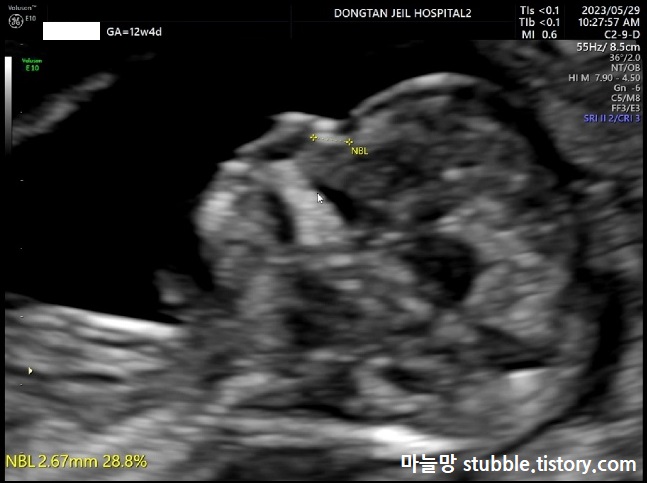

다운증후군의 경우 코뼈가 안 생기는 경우도 있다고 하여 코뼈를 확인합니다.

우리 아기는 코뼈도 잘 생겨 있었어요.

코뼈의 길이(NBL)는 2.67mm입니다.